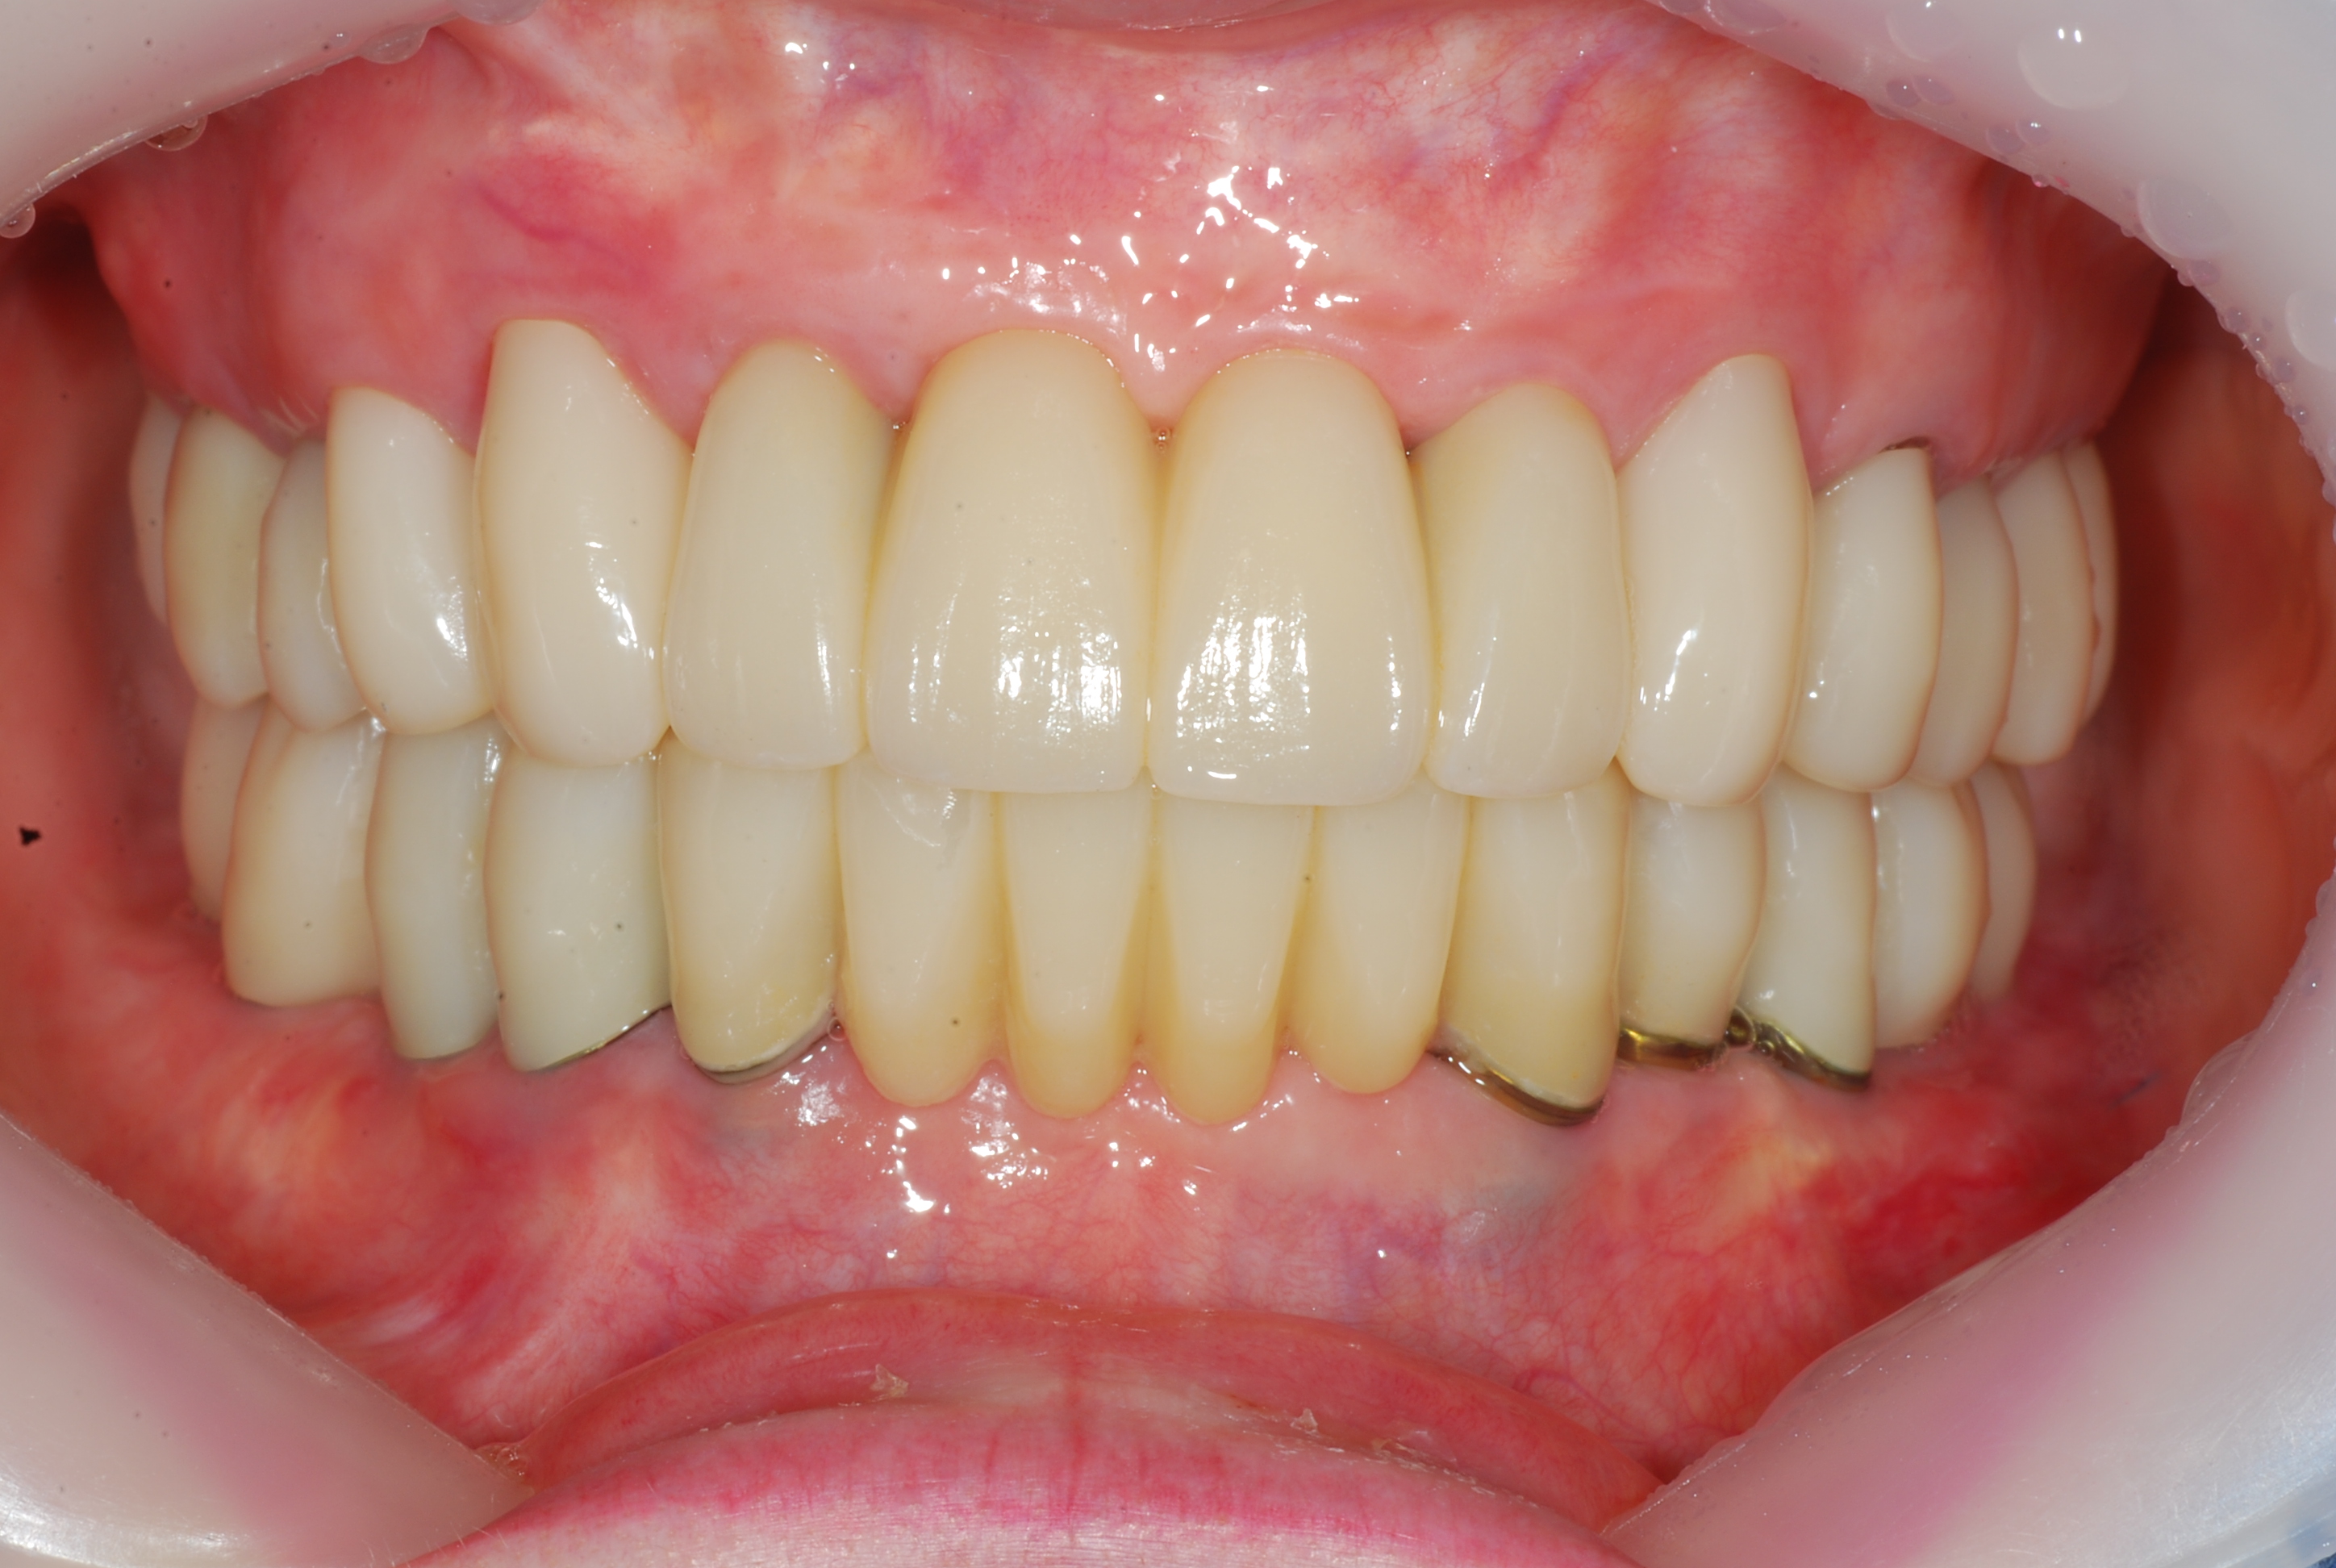

Full-mouth dental implants and prosthetics with sinus lift (upper jaw)

58 y.o, Kazakhstan

Operating dentist: Roh Hyun Ki